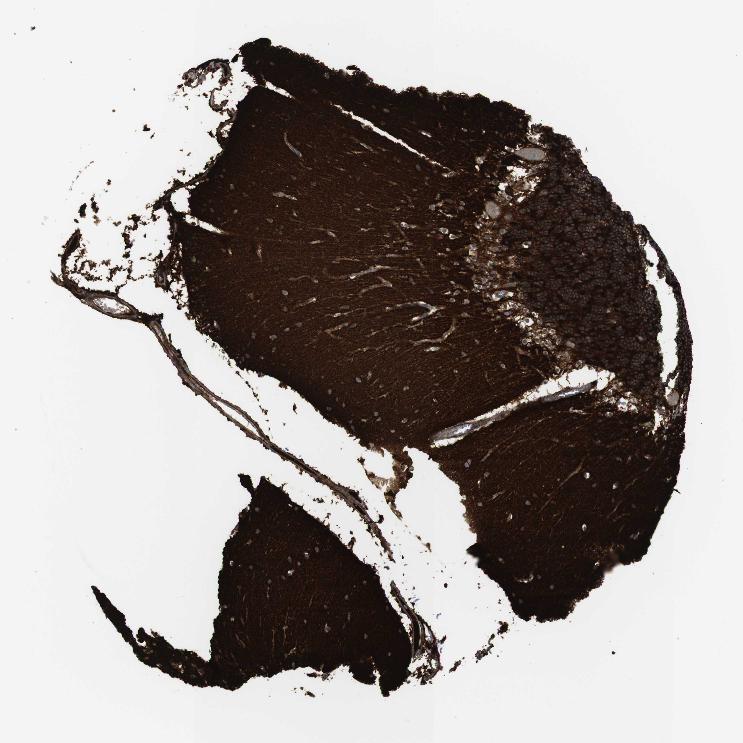

CEREBELLUM - Antibody stainingi

Antibody staining in the annotated cell types in the current human tissue is reported as not detected, low, medium, or high, based on conventional immunohistochemistry profiling in selected tissues. This score is based on the combination of the staining intensity and fraction of stained cells.

Each image is clickable and will lead to virtual microscopy that enables deeper exploration of all samples and also displays staining intensity scores, fraction scores and subcellular localization as well as patient and tissue information for each sample.

Antibody HPA054437Antibody HPA058511Antibody CAB002776Antibody CAB015122

Cells in granular layer High-HighHigh

Cells in molecular layer Not detected-MediumHigh

Molecular layer - neuropil -Medium--

Synaptic glomeruli - core -High--